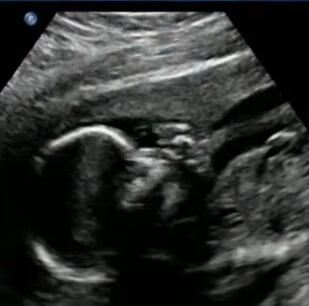

Nakon 9 meseci trudnoće, par dana pre terminaporođaja, Valeri je nažalost dobila tragičnu vest da je njena beba već mrtva. Ova mlada žena je bila slomljena. Stvar koja je pogoršavala situaciju jeste da je ostala sa praznom dečijom sobom, koja je bila puna igračaka i dečije garderobe.

- Cele nedelje sam znala. Nije se pomerao puno. Bila sam jako nervozna - rekla je Valeri o sedmici kada je saznala da je njen sin već mrtav.